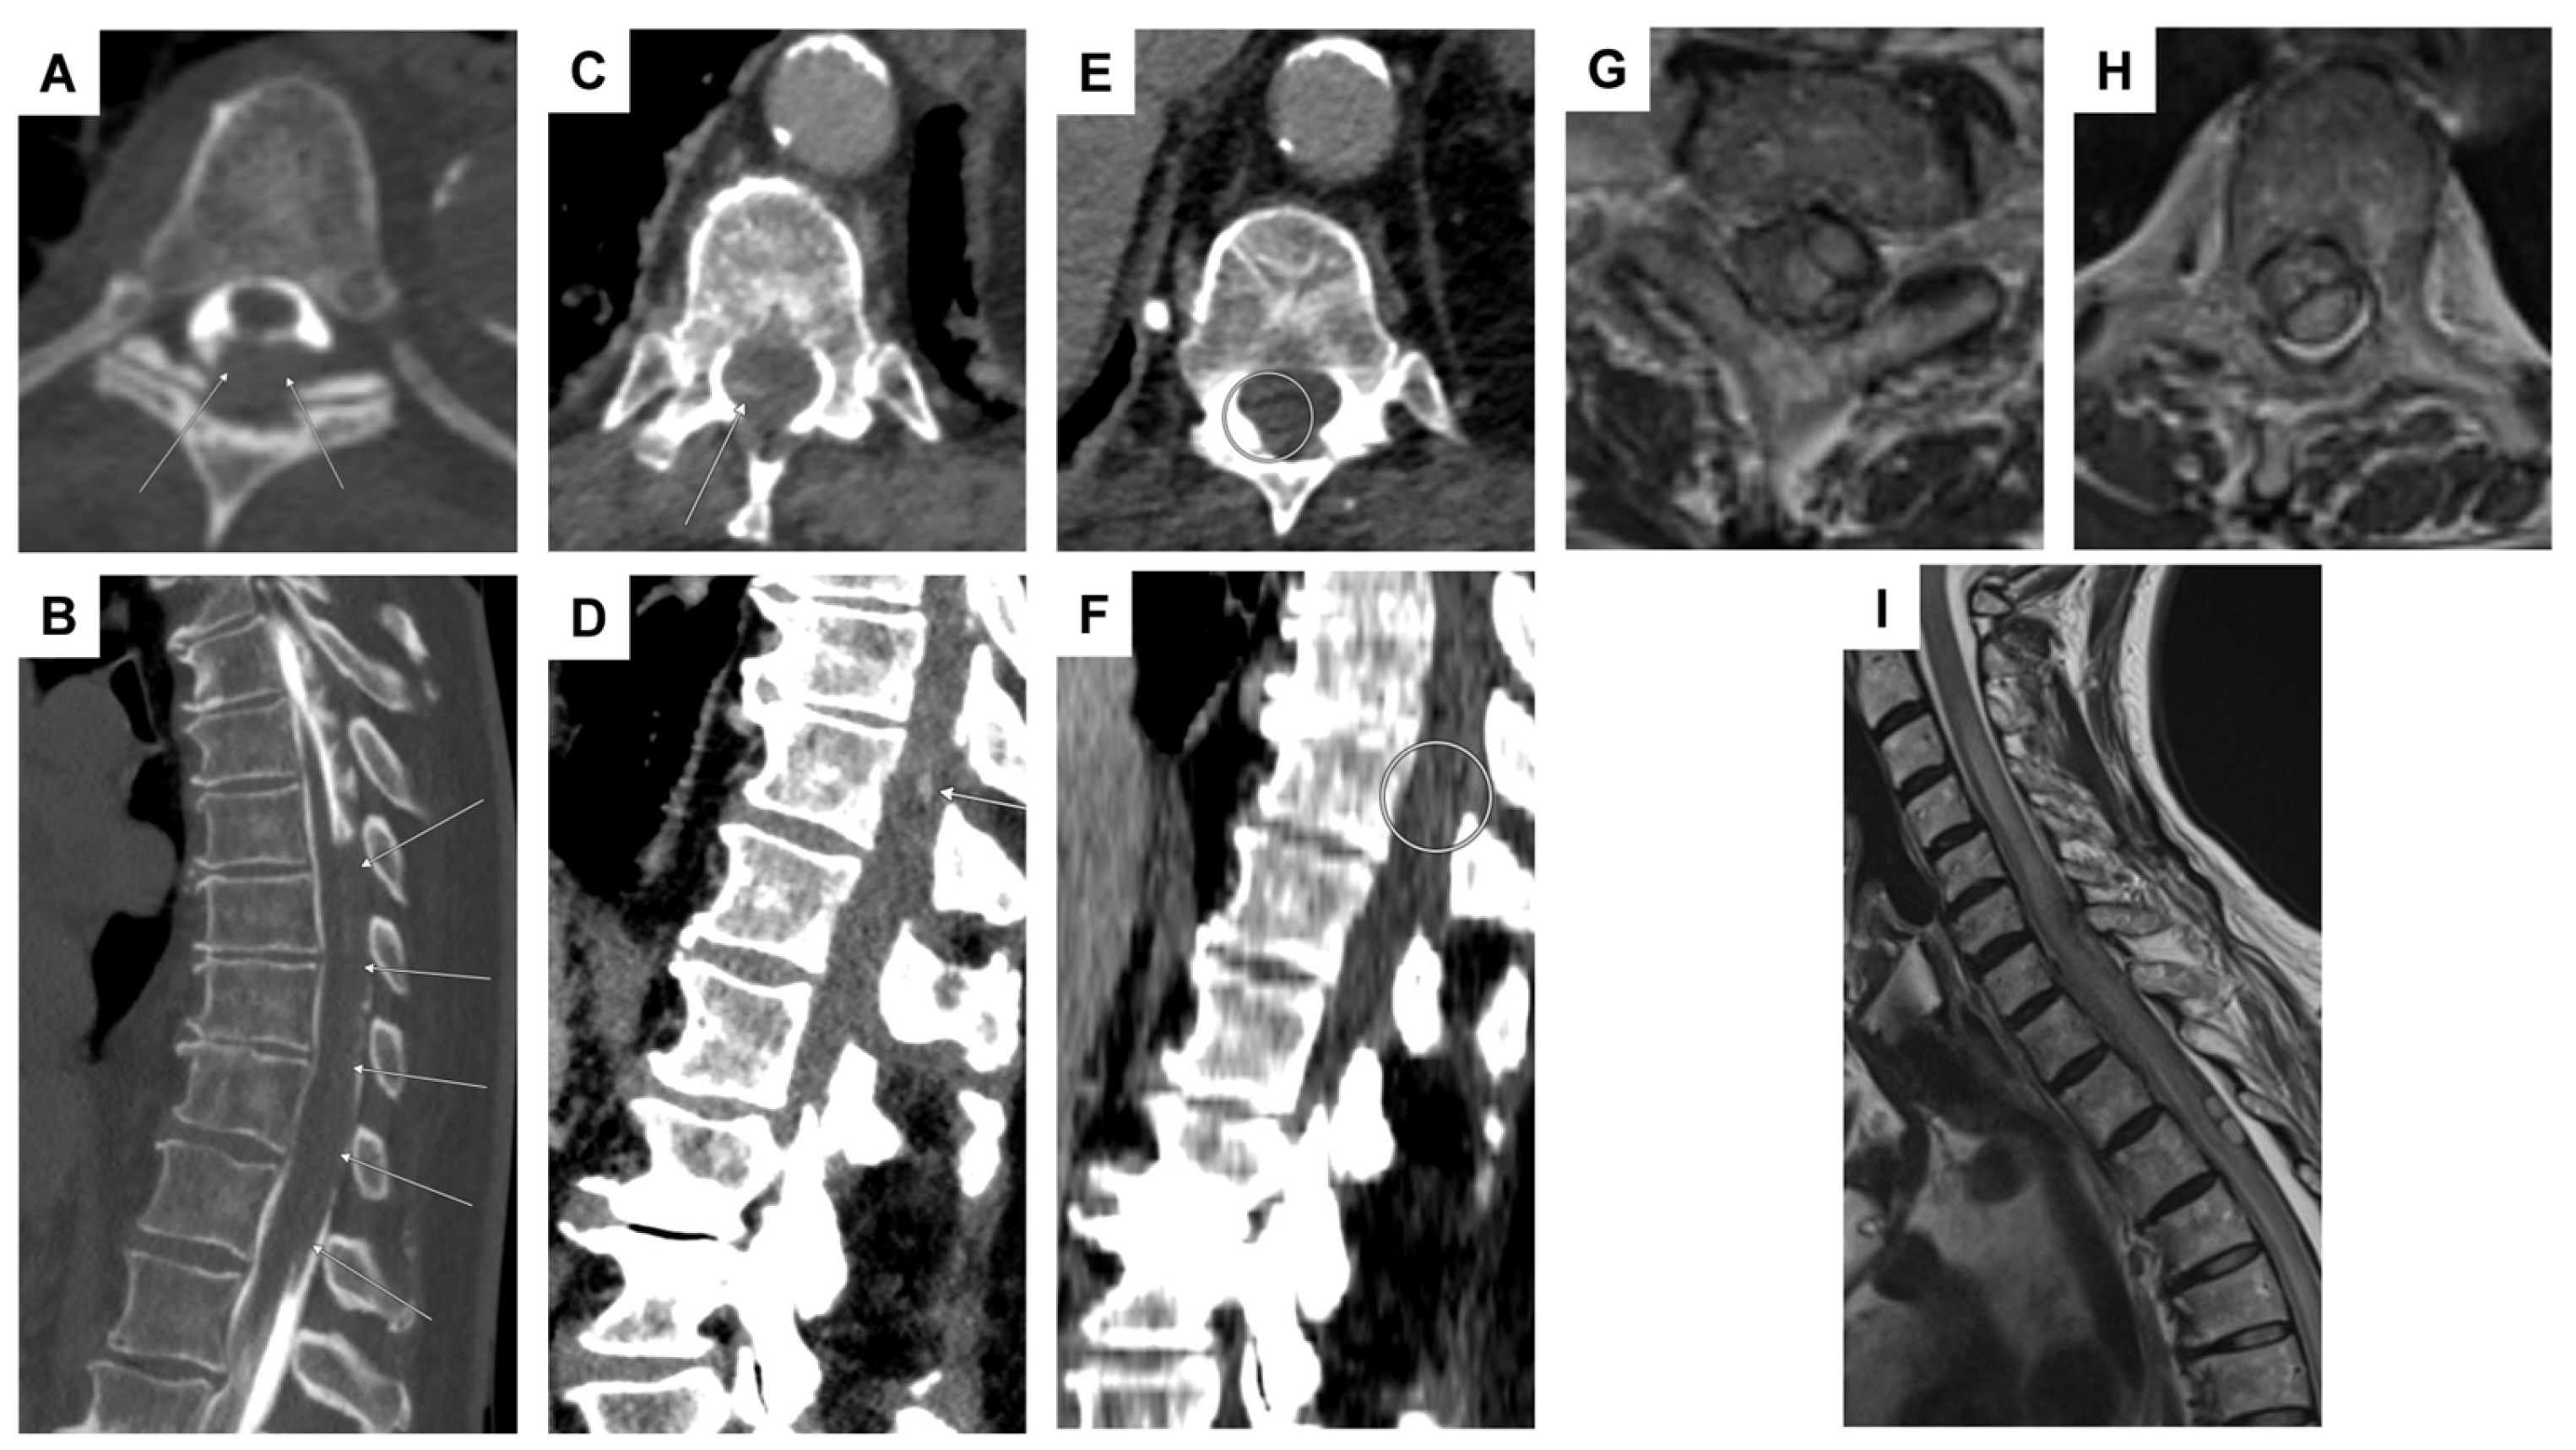

| 4 | F | 86 | iliosacral pain, paraparesis of the legs, and hypoesthesia from T11 | no evidence of manifest paralysis, intact sensation, unavailable reflexes in the lower extremities | spinal SAH; initially suspected T11 aneurysm; angiographically, no evidence of an aneurysm (spot sign) | anticoagulation (apixaban) | 2 lumbar punctures, repeated abdominal/thoracic CTA, DSA | conservative |

| 5 | F | 73 | headaches and pain in the back/neck pain | pronounced paraparesis of both legs | spinal SAH; angiographically, no evidence of an aneurysm | anticoagulation (rivaroxaban) | abdominal/thoracic CTA, multiple DSA, multiple spinal MRI | surgical procedure (evacuation of an intradural hematoma) |

| 6 | M | 55 | pain between the shoulder blades and the cervical spine, tingling sensations in all four extremities | tingling sensations in all extremities, unable to lift the legs, weakness in both arms | epidural bleeding and spinal SAH; suspected perimedullary aneurysm at T1/2; angiographically, no evidence of an aneurysm, epidural bleeding may be due to a microspur at T1/2 | microspur | multiple DSA, multiple spinal MRI | surgical procedure (evacuation of an epidural hematoma), then conservative (no evidence of an aneurysm) |